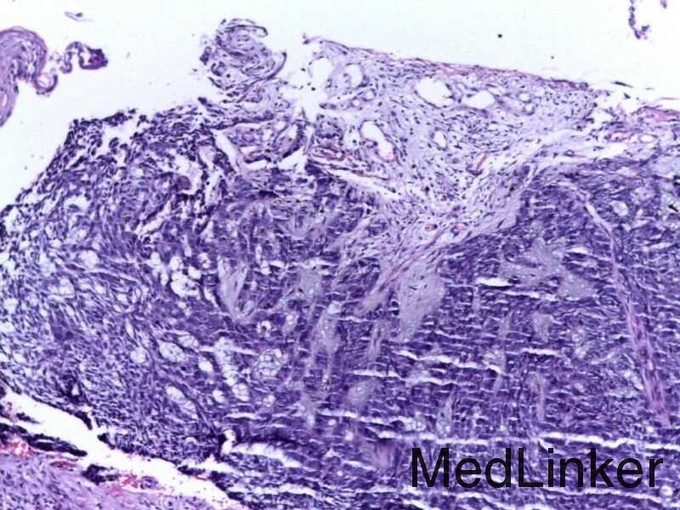

查体:腰背部中线上一孤立的黑褐色圆形皮肤肿物,表面溃烂,边缘清楚。 辅查:病理符合基底细胞癌病理改变

诊断:基底细胞癌。 处理:行肿物Mohs扩大切除术。术后随访。